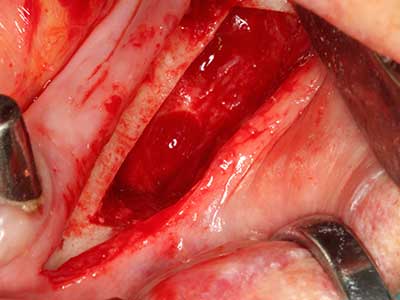

En la extracción de bloques óseos la piezocirugía también presenta ventajas adicionales: Además de la alta precisión en la osteotomía que ya se ha descrito antes, se ha comprobado que el uso de los delgados insertos de sierra resulta especialmente cuidadosas con el hueso. Frente a esto, sobre todo cuando se usan las fresas de Lindemann, cabe esperar pérdidas en la extracción significativamente más altas debido al mayor grosor de la parte frontal del cabezal (Lakshmiganthan, Gokulanathan et al. 2012). La separación basal que se necesita en particular en los injertos de bloque extraídos de forma retromolar se ve facilitada mediante sierras perpendiculares especialmente previstas a tal fin, lo que permite considerar que la cirugía piezoeléctrica es un procedimiento preciso y seguro para la obtención de bloques de hueso en el área retromolar (Happe 2007) (fig. 1-12).

Si es preciso realizar intervenciones quirúrgicas en las que el hueso está en contacto directo con estructuras sensibles, como son los vasos sanguíneos o los nervios, los instrumentos rotativos presentan un enorme potencial de provocar lesiones iatrogénicas. Así, precisamente en la representación de nervios después de una lesión iatrogénica, o en el transcurso de la lateralización de un nervio para resecciones, reconstrucciones o incorporación de implantes, los equipos piezoeléctricos pueden resultar muy útiles para preparar la tapa ósea y retirar las partes de tejido duro cercanas al nervio (fig. 17-20). Por lo general, un ligero contacto del cordón nervioso con el inserto piezoeléctrico no tiene consecuencia alguna; ahora bien, un procedimiento poco cuidadoso con movimientos tipo sierra o piezas de trabajo sobre la base ósea aún existente puede provocar lesiones nerviosas temporales o incluso permanentes. Con todo, el riesgo de sufrir una lesión de este tipo se considera significativamente inferior que en los casos en los que se utilizan sierras y fresas (Pereira, Gealh et al. 2014).